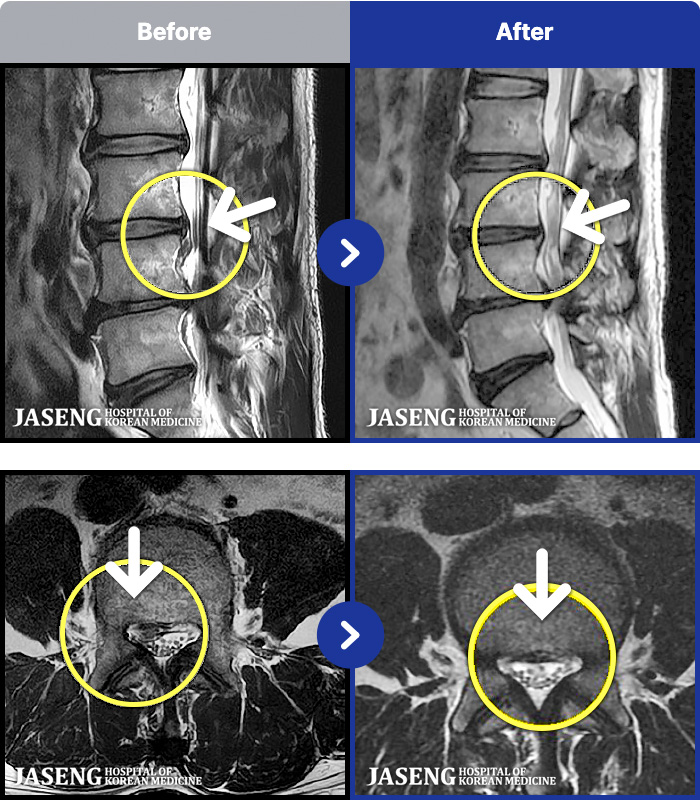

MRI ġ

54 MRI ũ ʸ Ȯϼ.

[Կñ:22.04.11~22.07.28]

[_㸮ũ] Ͽ ü Ÿ Ͽϴ.